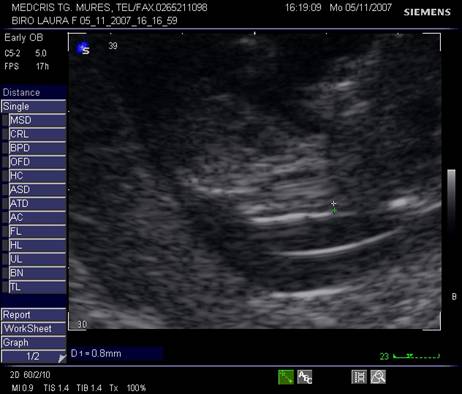

Fig. nr.128 Pliu nuchal cu dimensiunea de 2,9 mm.Cu sageata se remarca alaturat amniosul, magnificatia redusa nu permite obtinerea unei imagini optimale a translucentei nuchale.

Fig. nr.129 Masurarea pliului nuchal la o marire corespunzatoare

Masurarea NT egala sau peste 3 mm este considerata anormala. Riscul defectelor cromozomiale creste marcat in functie de marimea NT si de varsta mamei, necesitand punctie biopsie de vilozitati choriale sau amniocenteza.

Cea mai buna metoda de screening [18] ramane asocierea varstei materne, masurarea translucentei nuchale si nivelul seric matern de HCG β- human chorionic gonadotropin si PAPP-A (Pregnancy associated plasma protein- A) la 11 - 14 sapt gestationale ( dublu test ). Detectarea defectelor cromozomiale este in jur de 90%, cu ajutorul unui soft ce integreaza aceste date si efectueaza calculul riscului relativ.